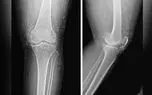

کشف صدها رشته طلای خالص در زانوی زن مبتلا به آرتروز

زانو درد این بیمار با وجود استفاده از درمان های دارویی مانند مسکن، داروهای ضد التهاب غیر استروئیدی و حتی تزریق استروئید بهبود نیافت و حتی عارضه معده درد شدید را داشت. به همین دلیل او به طب جایگزین بحث برانگیز طب سوزنی با نخ طلا روی آورد.